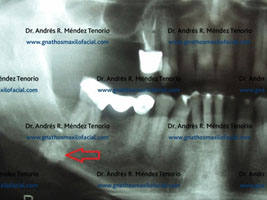

Imágenes de la lesión, caracterizada por tejido mineralizado en el conducto de la glándula submandibular

Condición resuelta una vez que se retira quirúrgicamente el sialolito